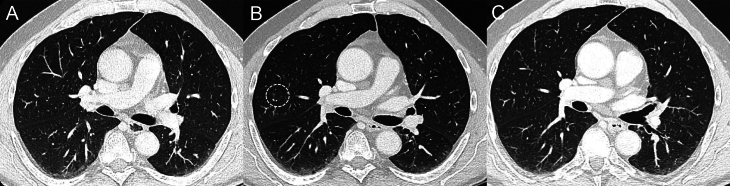

高选择性RET抑制剂赛帕替尼对晚期/进展期RET突变甲状腺髓样癌(MTC)患者有显著疗效。然而,尽管该药的毒性比多激酶抑制剂更易耐受,但也出现了一些特殊的不良事件(AEs)。闭塞性细支气管炎(OB)是一种以小传导气道炎症和纤维化为特征的呼吸系统疾病。我们对一名70岁的晚期RET突变MTC患者进行了评估,该患者在接受赛帕替尼治疗期间出现了阻塞性支气管炎。OB的放射学特征出现较早,并在赛乐替尼治疗期间持续存在,呈消长模式。值得注意的是,在治疗期间,MTC 获得了部分应答,而舍培卡替尼从未减量或中断。OB几乎完全没有症状,而且呈波动趋势,没有针对OB的特殊治疗,这表明有必要仔细评估这种AE介导的风险以及修改或中断抗癌疗法的风险。

Highly selective RET inhibitor selpercatinib has demonstrated notable efficacy in advanced/progressive RET-mutant medullary thyroid cancer (MTC) patients. However, despite a more tolerable toxicity profile than multikinase inhibitors, peculiar adverse events (AEs) have been described. Obliterative bronchiolitis (OB) is a respiratory disease characterized by inflammation and fibrosis in small conducting airways. We evaluated a 70-year-old man with advanced RET-mutant MTC who developed OB during treatment with selpercatinib. Radiological features of OB occurred early and persisted during selpercatinib treatment, with a waxing and waning pattern. Notably, a partial response of MTC was achieved during the treatment, and selpercatinib was never reduced or interrupted. The almost complete absence of symptoms and the fluctuating trend, without specific treatment for OB, suggested that it is necessary to carefully evaluate the risks mediated by this AE with the risks of modifying or discontinuing the anti-cancer therapy.